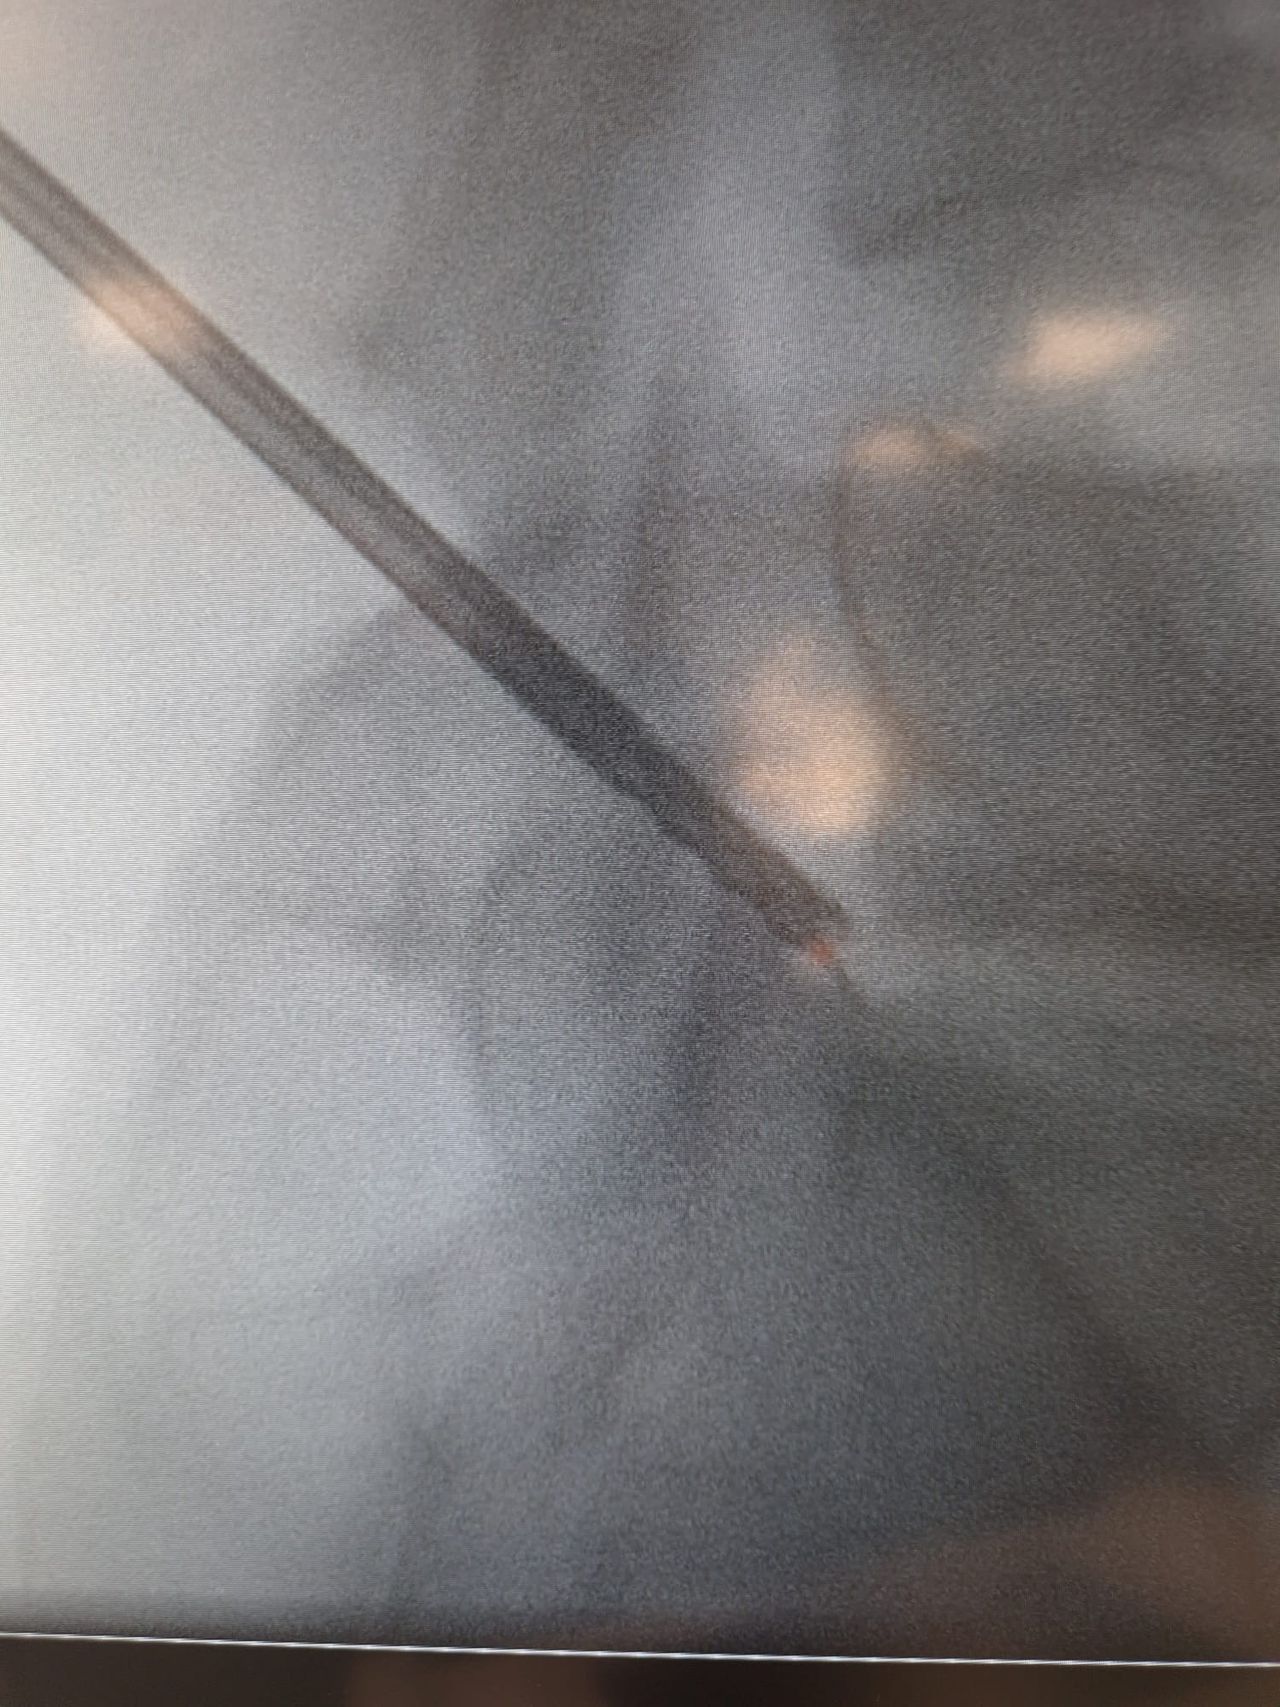

Starszy Asystent w Klinicznym Oddziale Neurochirurgicznym oraz Poradni Neurochirurgii Wojewódzkiego Szpitala Specjalistycznego im. św. Barbary nr 5 w Sosnowcu. Konsultant Kliniki Neurologii Szpitala Klinicznego nr 1 w Zabrzu. Absolwent Wydziału Lekarskiego Śląskiego Uniwersytetu Medycznego w Zabrzu. Staż podyplomowy odbył w latach 2010-2011 w Oddziale Neurochirurgii WSS nr 4 w Bytomiu. W 2018r. złożył egzamin specjalizacyjny po zakończeniu szkolenia w ramach rezydentury w WCM Opole. W 2019 roku uzyskał stopień doktora nauk medycznych. Specjalizuje się w kompleksowym leczeniu schorzeń kręgosłupa (dyskopatia, stenoza kanału kręgowego, kręgozmyk) oraz neuroonkologii. Szczególny zakres działań medycznych to nowoczesne, małoinwazyjne operacje kręgosłupa z wykorzystaniem technik endoskopowych (mikrodiscektomia - implanty rozprężalne), przezskórnych stabilizacji oraz mikrochirurgicznych dekompresji. Wykonuje procedury iniekcyjne; discoGEL, GelSTIX, kriolezje oraz blokady przeciwbólowe kręgosłupa odcinka szyjnego, lędźwiowo-krzyżowego a także stawów krzyżowo-biodrowych, które odgrywają istotną rolę w procesie diagnostyczno-leczniczym wielu zespołów bólowych. Na co dzień przeprowadza operacje w ramach kontraktu z NFZ. Członek Polskiego Towarzystwa Neurochirurgów oraz Polskiego Towarzystwa Chirurgii Kręgosłupa. Uczestnik wielu krajowych i zagranicznych kursów neurochirurgicznych, m.in. w Czechach, Słowacji, Niemczech, Włoszech, Danii, Austrii, Szwajcarii i USA. Autor licznych publikacji naukowych.

Zdjęcia i filmy